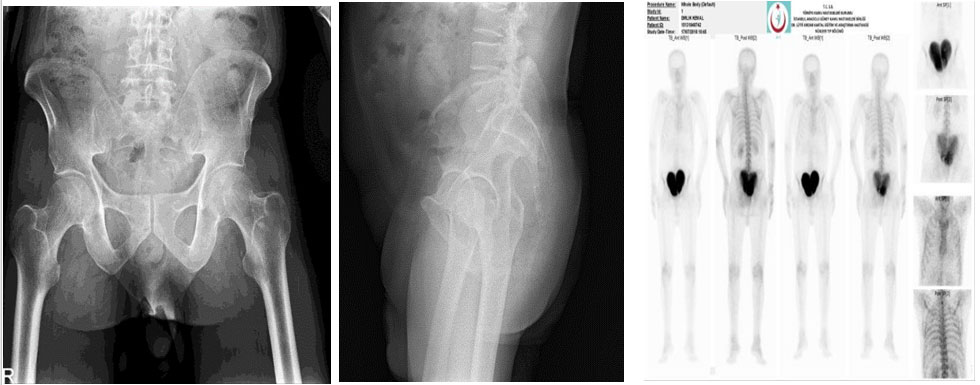

Ameliyat öncesi: Röntgende sakrum ve koksiksde harabiyet, sintigrafide yoğun artmış aktivite görülmekte